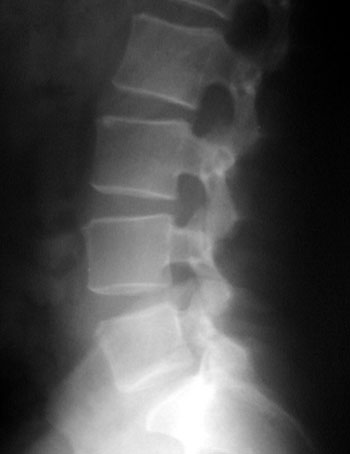

Foram realizadas radiografias onde, não sendo encontradas alterações significativas (Fig. 6); optado então por realizar ressonânca magnético sendo evidenciada uma hernia contida L4-L5 (Fig. 7).

Fig. 6a

Fig. 6b